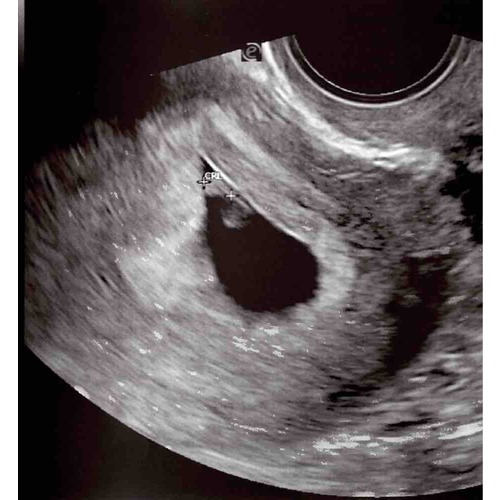

Vandaag de eerste echo gehad! Iets minder ver dan gedacht, 7+1 en een mooi kloppend hartje🥰 wie durft een gok te doen?😜💙💗 dit is een inwendige echo!

Vandaag de eerste echo gehad! Iets minder ver dan gedacht, 7+1 en een mooi ...

💙